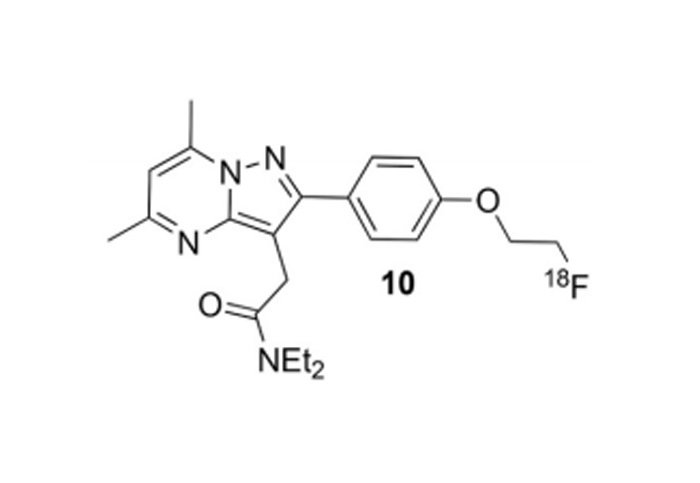

對(duì)18F、11C、68Ga、等核素示蹤劑的(de)合成與國(guó)外(wài)主流示蹤劑合成平台達到(dào)同一(yī)水(shuǐ)<平;